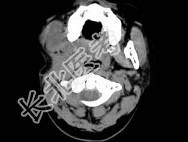

- 单项选择题男,30岁, 感右下颌部有一肿物,逐渐肿大, 胀痛,局部麻木1月余, 结合图像,最可能的诊断是 ( )

A、神经纤维瘤

B、神经鞘瘤

C、血管瘤

D、下颌骨肉瘤

E、软骨瘤